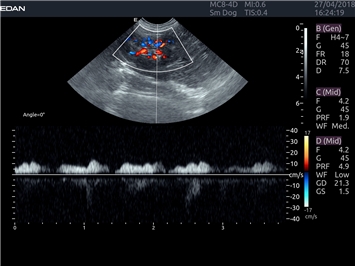

EDAN Acclarix LX4 VET представляет собой профессиональную ультразвуковую систему, специально разработанную для ветеринарных исследований. Сочетание стабильности, высокой производительности и эффективности делает эту систему идеальным выбором для современной ветеринарной практики.

Инновационные технологии обработки изображений:

• Адаптивная визуализация тканей:

• Оптимизация изображения для различных видов животных

• Улучшенная детализация структур

• Мультилучевое сложно-составное сканирование (SCI):

• Повышенная четкость изображения

• Улучшенная визуализация сложных анатомических структур

• Технология подавления зернистости:

• Снижение шумов изображения

• Повышение диагностической ценности

Цветовой допплер:

Да

Импульсно-волновой допплер: